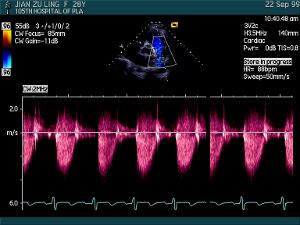

在二維或 M型圖像監視定位下,利用都卜勒原理,採用距離選通技術,將取樣容積放在心臟或大血管內一定部位,取一定容積的血流信息,經快速傅立葉變換,實時地以頻譜的方式顯示某點的血流速度、方向和性質。據此可以判斷各瓣膜口有無狹窄、返流,了解心內有無分流,並且計算心排血量和跨瓣口的壓力階差。

血液在正常人心臟和大血管內流動時,其血流方向相同,但其橫截面上各點的流速不同。研究證明,流經各瓣口的血流為層流,其頻譜特點為頻譜窄、光點密集,中間空虛,音頻輸出可聽到柔和平滑的都卜勒聲。當血流經過狹窄的瓣膜或管腔時,血流速度增加,血流方向和速度均不相同,產生湍流,其特點是頻譜寬,光點分散,中間充填,可聽到粗糙刺耳的血流聲。血流過快測量將受限制。

頻譜圖的縱坐標反映血流的方向和速度,血流朝向探頭流動即產生向上的頻移,反之則產生向下的血流圖,頻移幅值代表血流速度的高低;橫坐標代表時間。